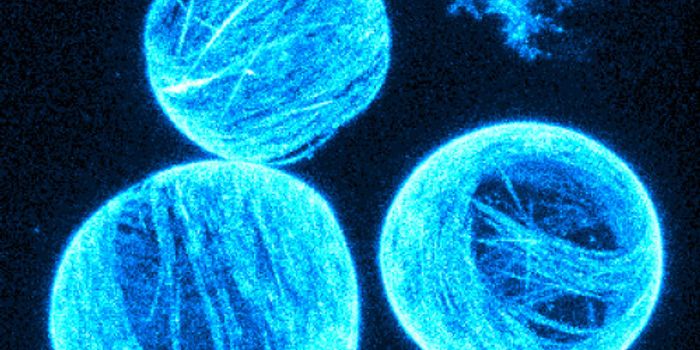

JUL 17, 2015NeuroscienceWhat causes autism? Is there something physical that accounts for behavioral differences?

APR 09, 2015NeuroscienceA new study by UNC researchers, based on MRI brain scans of 152 infants, found disruptions in functional connectivity wi ...